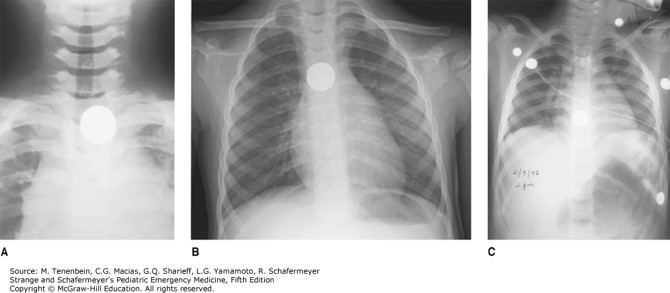

Figure 12-2 of the Foreign Bodies chapter highlights the three most common sites for esophageal foreign body: A. thoracic inlet (60%–70%); B. mid-esophagus (10%–20%); C. lower esophageal sphincter (20%).